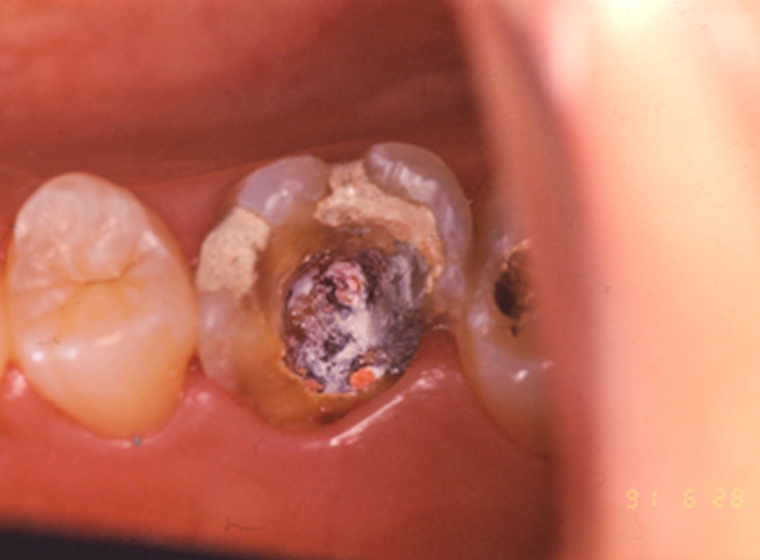

- 歯に汚れがたまりやすいので、むし歯や歯周病にかかりやすくなります

治療中のむし歯予防に力を入れています

セルフケアの仕方をアドバイスします。また調整の際にはクリーニングやブラッシングのアドバイスなど、むし歯予防のための取り組みを行っています。

- STEP4治療前の準備

- 治療にご同意いただけましたら、治療開始です。必要に応じてむし歯や歯周病などの治療を行います。